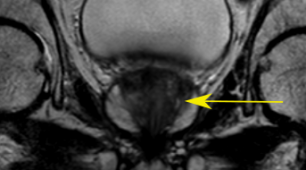

Fig. 4: SR result for anisotropic SRGAN using real data, yellow arrow indicates suspicious cancer region

Figure 4 is an example of axial and coronal views. The HR views portray the difference in resolution between the in-plane axial slice and the coronal and sagittal through-plane slices. The SR views show the anisotropic SRGAN outputs on the real HR data. The arrows in the top row of Figure 4 point to a suspicious region within the axial prostate. The LR axial image obtained by taking a through-plane slice from a coronal volume has lost all information about this region. The SR image is able to reconstruct the high frequency content and provides valuable edge and texture information. The anisotropic SRGAN method is able to improve the through-plane resolution by 8x while incurring only a slight resolution loss in the in-plane slice.